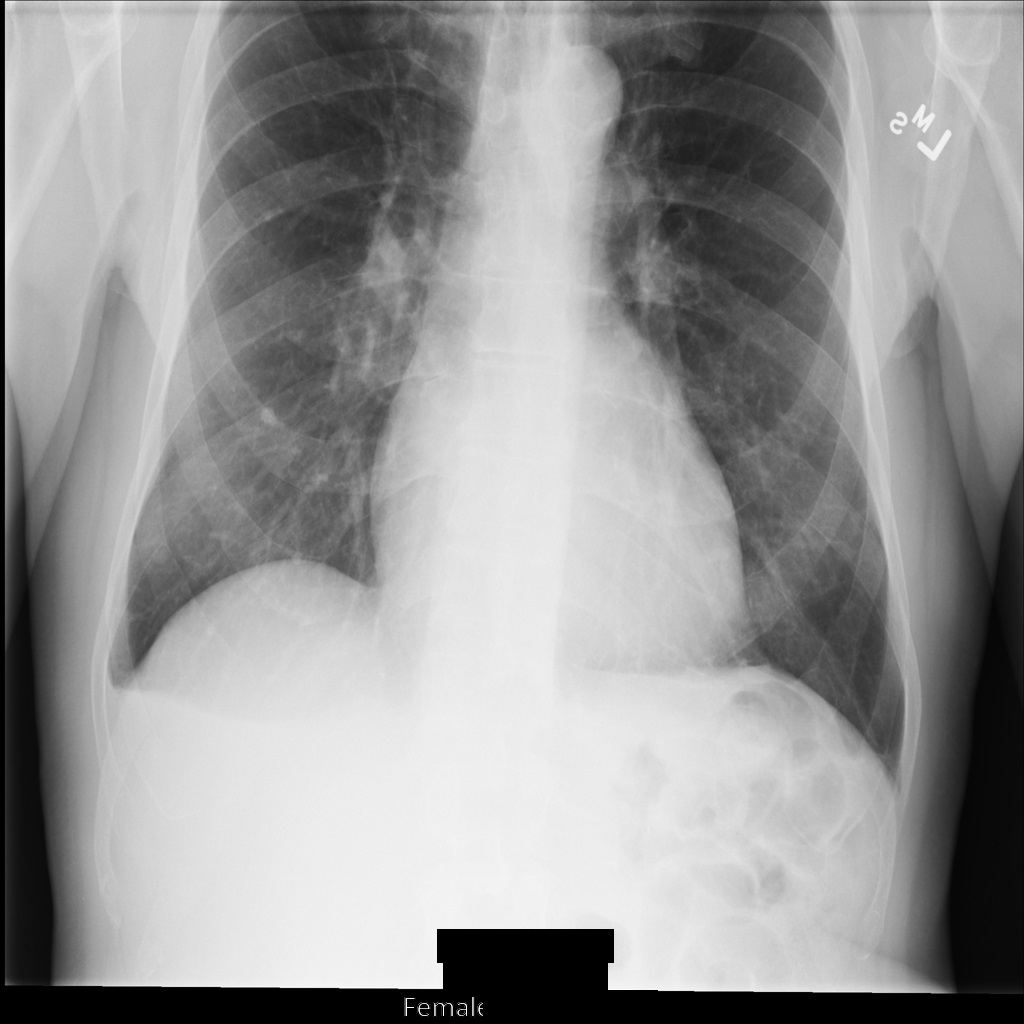

After de-identifying the image using REDACT_SENSITIVE_TEXT_CLEAN_DESCRIPTORS, the image

looks like this. Notice that not all the burned-in text at the bottom of the

image has been redacted. The text Female is still shown, because

PatientSex (0010,0040) isn't one of the default DICOM infoTypes.